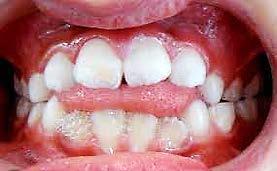

Caries y pérdida dental

La formación de caries en la dentición decidua y la consecuente pérdida prematura de órganos dentales deciduos, en algunas ocasiones, son

consideraciones a tomar muy en cuenta como factor etiológico en la inclusión del canino (Figura 32).

Por un lado, la presencia de caries interproximales en dientes deciduos, ya sea de manera independiente o como consecuencia de caries rampantes en uno o varios dientes, propicia la disminución de la longitud y/o perímetro del arco dental, donde ya no habrá, en consecuencia, el espacio necesario para el acomodo definitivo de los caninos y premolares permanentes.14

Por otro lado, al haber una pérdida prematura de un diente deciduo, además de generar una disminución de la longitud del arco dental, la biomecánica fisiológica propia de nuestro organismo, tiende a cerrar los espacios o brechas generadas por la pérdida de algún órgano dental, mesializando los dientes distales al diente faltante y generando extrusión del antagonista inmediato (Figura 33).

En consecuencia, los dientes que están en formación en cualquier periodo de Nolla quedaran atrapados dentro del hueso basal, con

posibilidades limitadas o nulas de acceder al hueso alveolar y erupcionar en la posición correcta, donde los caninos por todo lo mencionado anteriormente, son los más afectados.13

Alteraciones faciales

Todos los dientes intervienen en la conformación de una oclusión ideal, así como del volumen facial en el tercio medio e inferior de la cara. Es el caso, que la presencia del canino superior permanente en la arcada en el tiempo cronológico adecuado, es muy importante para el desarrollo óseo del tercio medio facial, ya que estimula el crecimiento del maxilar tanto en el área lateral del ala de la nariz bilateralmente, como en la pared anterior del macizo óseo, lo cual, evita el hundimiento facial de la parte inferior del pómulo y la rectificación facial de los músculos en esta área15 (Figura 34).